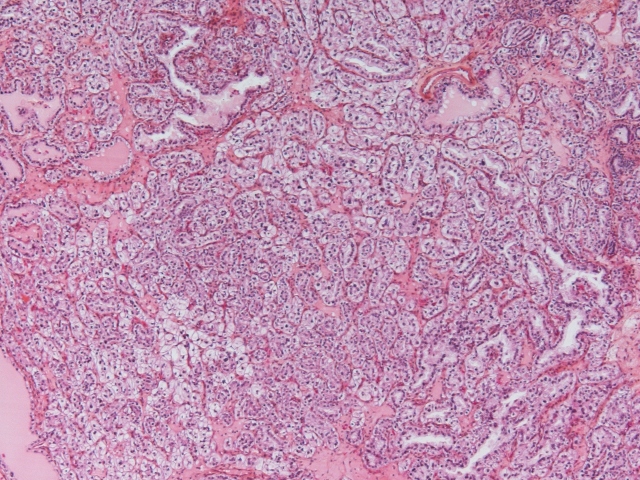

Classification of renal tumors

Case ID: 963

21 Jan, 2016